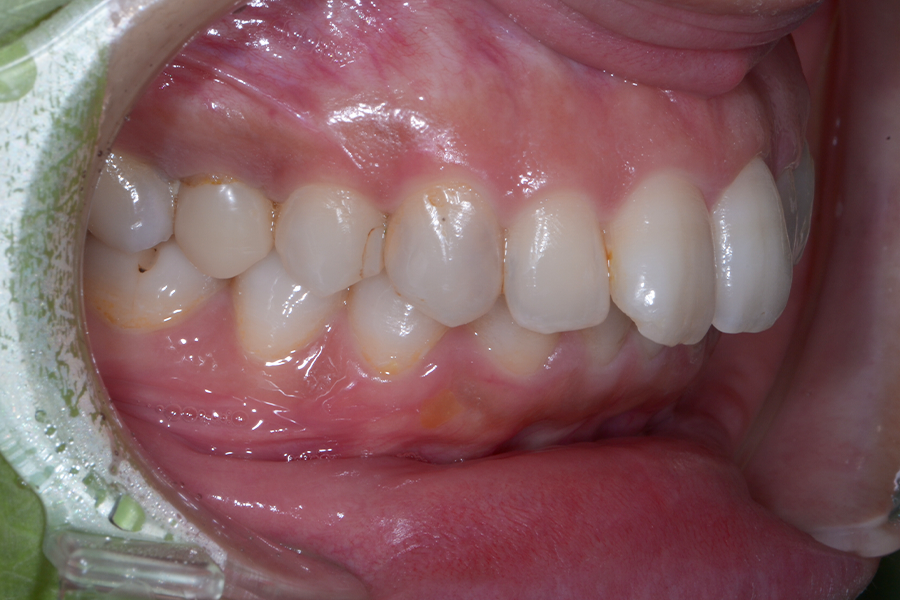

• 治療前